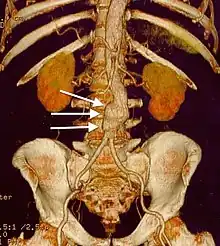

| CT reconstruction image of an abdominal aortic aneurysm (white arrows) | |

Sagittal CT image of an AAA